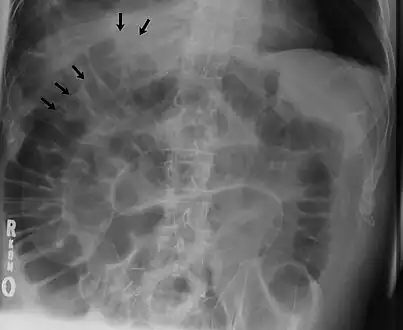

Double wall sign. This is a secondary sign of pneumoperitoneum. Patient is supine, and air within the abdomen and lumen of the bowel accentuate both sides of the bowel wall.- Ultrasound finding of pneumoperitoneum known as "peritoneal stripe sign"[24]

The double wall sign marks the presence of air on both sides of the intestine.[19] However, a false double wall sign can result from two loops of bowel being in contact with one another.[20] The sign is named after Leo George Rigler.[21] It is not the same as Rigler's triad.

Signs that can be seen on projectional radiography are shown below: